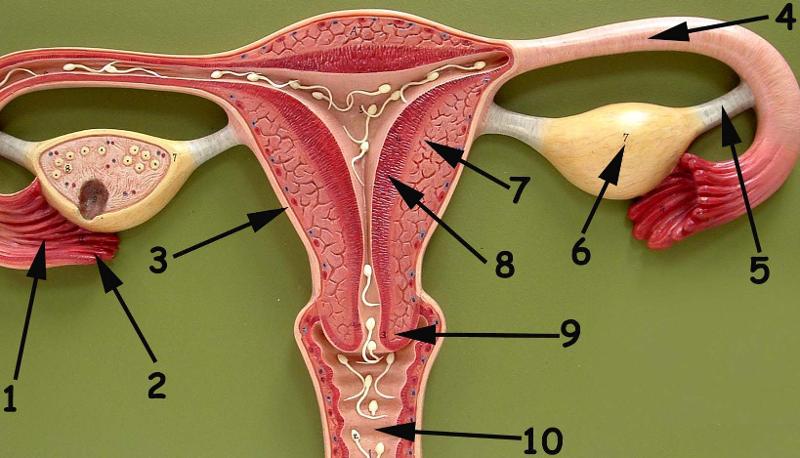

Broad ligament

Cervix

Corpus luteum

Endometrium

Fimbriae

Mature (=Graafian, = antral) follicle

Myometrium

Overian ligament

Ovary

Perimetrium

Primordial/primary/secondary follicle

Round ligament (of uterus)

Uterine (=fallopian) tube

Uterus

Vagina

Vaginal orifice